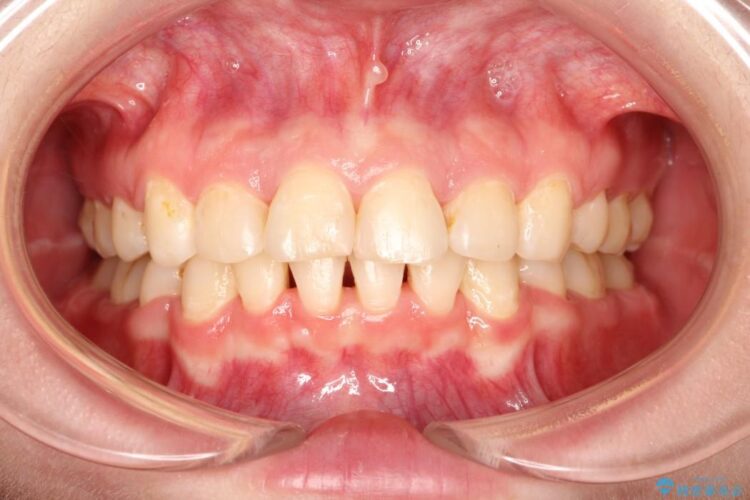

口元が出ていることを気にされて来院されました。

出ている歯を引っ込めるためのスペースを作るため、上下左右の小臼歯を抜歯し、ワイヤー矯正を行いました。治療後は、口元がスッキリとしたことで患者様にも喜んでいいただきました。